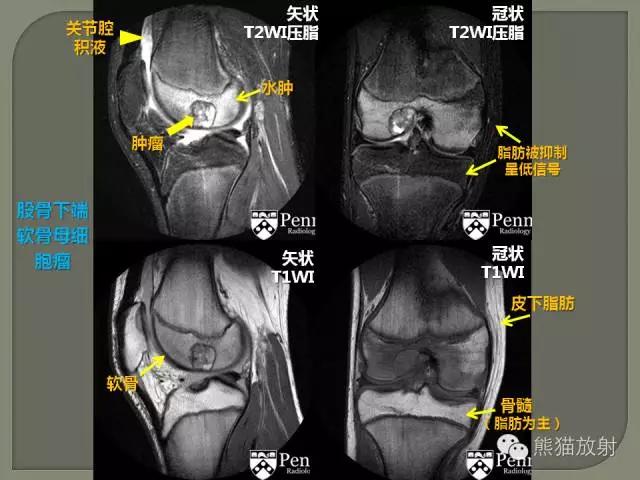

脂肪、骨髓不论在T1WI、T2WI和PDWI(质子加权像)图像上均呈高信号

肌肉、肌腱、韧带:肌肉在T1WI、T2WI和PdWI上均呈中等强度信号(黑灰或灰色)。肌腱和韧带组织含纤维成分较多,其质子密度低于肌肉,其信号强度较肌肉组织略低,该组织也有长T1和短T2,其MR信号为等信号或较低的信号。

骨骼、钙化:T1WI、T2WI和PDWI图像上均呈信号缺如的无(低)信号区。

软 骨:在T1、T2加权像上信号强度不高,呈中低信号

血 流:快速流动的血液因其“流空效应”,在各种成像上均低(无)信号血管影;而缓慢或不规则的血流,如:湍流、旋流等,血管内信号增加且不均匀。